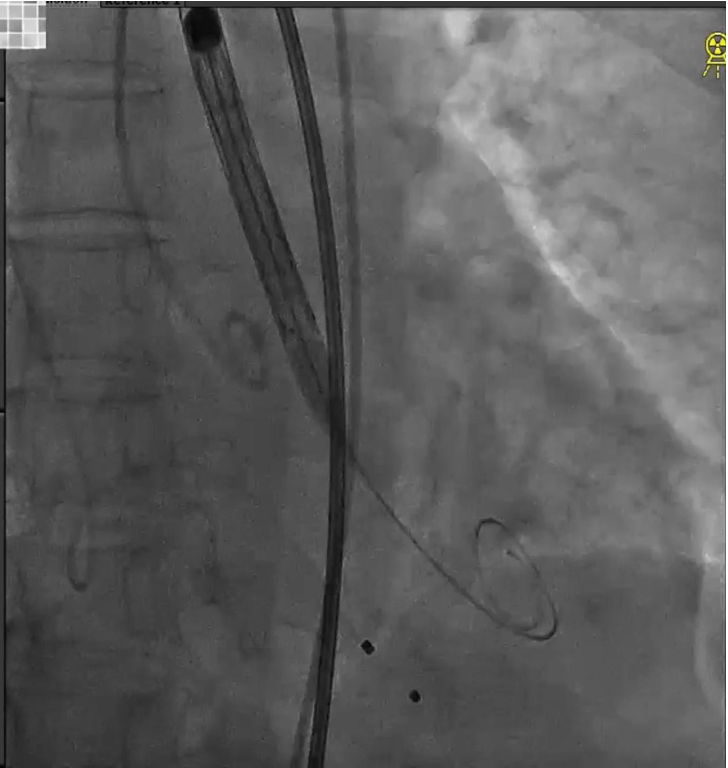

主动脉弓造影,观察头臂干、颈总动脉和左锁骨下动脉形态;

脑保护输送系统置入;

导丝跨瓣;

猪尾导管交换预塑形导丝;